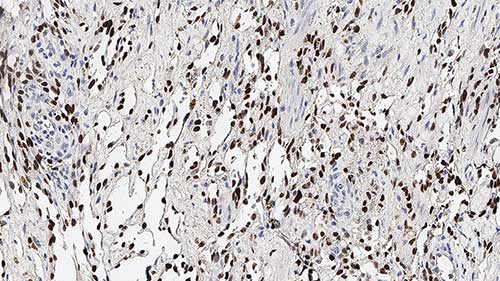

Human thymoma: immunohistochemical staining for CD1a. Note the neoplastic cells show a moderate to strong and distinct membrane staining reaction. CD1a: clone MTB1

Clone MTB1 detects cortical thymocytes, Langerhans cells in epidermis, interdigitating cells of dermis and interdigitating cells of stratified squamous epithelium of tonsil. Clone MTB1 may also detect small focal groups of lymphocytes outside the germinal centers of tonsil indicating a cross-reaction with CD1b antigen.